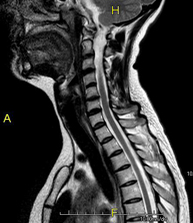

- RM de columna cervical

Prova diagnòstica no invasiva que consisteix en l'obtenció d'imatges d'alta definició anatòmica de la columna cervical mitjançant l'ús d'un camp electromagnètic i ones de ràdio (com un emissor i un receptor). No utilitza radiació ionitzant. Indicacions: traumatisme, degeneració de la columna, hèrnies. - RM de columna dorsal

- RM Columna Cervical

Prova diagnòstica no invasiva que consisteix en l'obtenció d'imatges d'alta definició anatòmica de la columna cervical, mitjançant l'ús d'un camp electromagnètic i ones de ràdio (amb un emissor i un receptor). No utilitza radiació ionitzant. Indicacions: traumatisme, degeneració de la columna i hèrnies. - RM Columna Dorsal